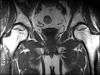

Femur başı avasküler nekrozu bir sebeple( yüksek doz yada sürekli steroid kullanımı, travma) ve ya sebebi bulunamayan bir şekilde uyluk kemiğinin ( femur) baş kısmında kan dolaşımının bozulmasına bağlı kemik ölümünün gerçekleşmesidir. Beslenmesi bozulan kemik gücünü kaybeder ve hastanın bu durumdayken ayakta dolaşması sebebiyle üzerine binen yükler sebebiyle yuvarlaklığını kaybederek çöker. Anatomik yapısı bozulan eklemde zamanla kireçlenme (artroz) gelişir. Femur başı avasküler nekrozu ilerleyici bir hastalıktır. Kalçada ilk başlarda hareketle artan ağrı zamanla süreklilik kazanır. Ağrı ve aksama şikâyetiyle doktora başvuran hastalarda klinik bel fıtığı ile karıştırılabilir. Hastalığın erken evrelerinde standart röntgen grafileri ile tanı konulamayabilir. İlgili hekimin hastalıktan şüphelenmesi sonucu çekilen MRI görüntüleme tanı koydurucudur. Tanı konulan hasta mutlak suretle tedavi girişimi yapılıncaya kadar etkilenen bacağı üzerine yük vermeyi azaltmalı mümkünse koltuk değneği kullanmalı ve ayakta kalma ya da spor aktivitelerinden uzak durmalıdır. Tedavi edilmeyen hastalarda hastalığın ilerleme oranı %80 ve üzeridir. Hastalığın ileri yaşlarda (50 ve üzeri) görüldüğü durumlarda total kalça protezi ile tedavi edilmesi mükemmel sonuçlar verebilir. Ancak genç hastalarda erken dönemde protez kullanılması ileride proteze bağlı gevşeme, revizyon gibi komplikasyonlar sebebiyle tercih edilmemektedir. Bu sebeple genç hastalarda eklem koruyucu tedavi yöntemleri geliştirilmiştir.